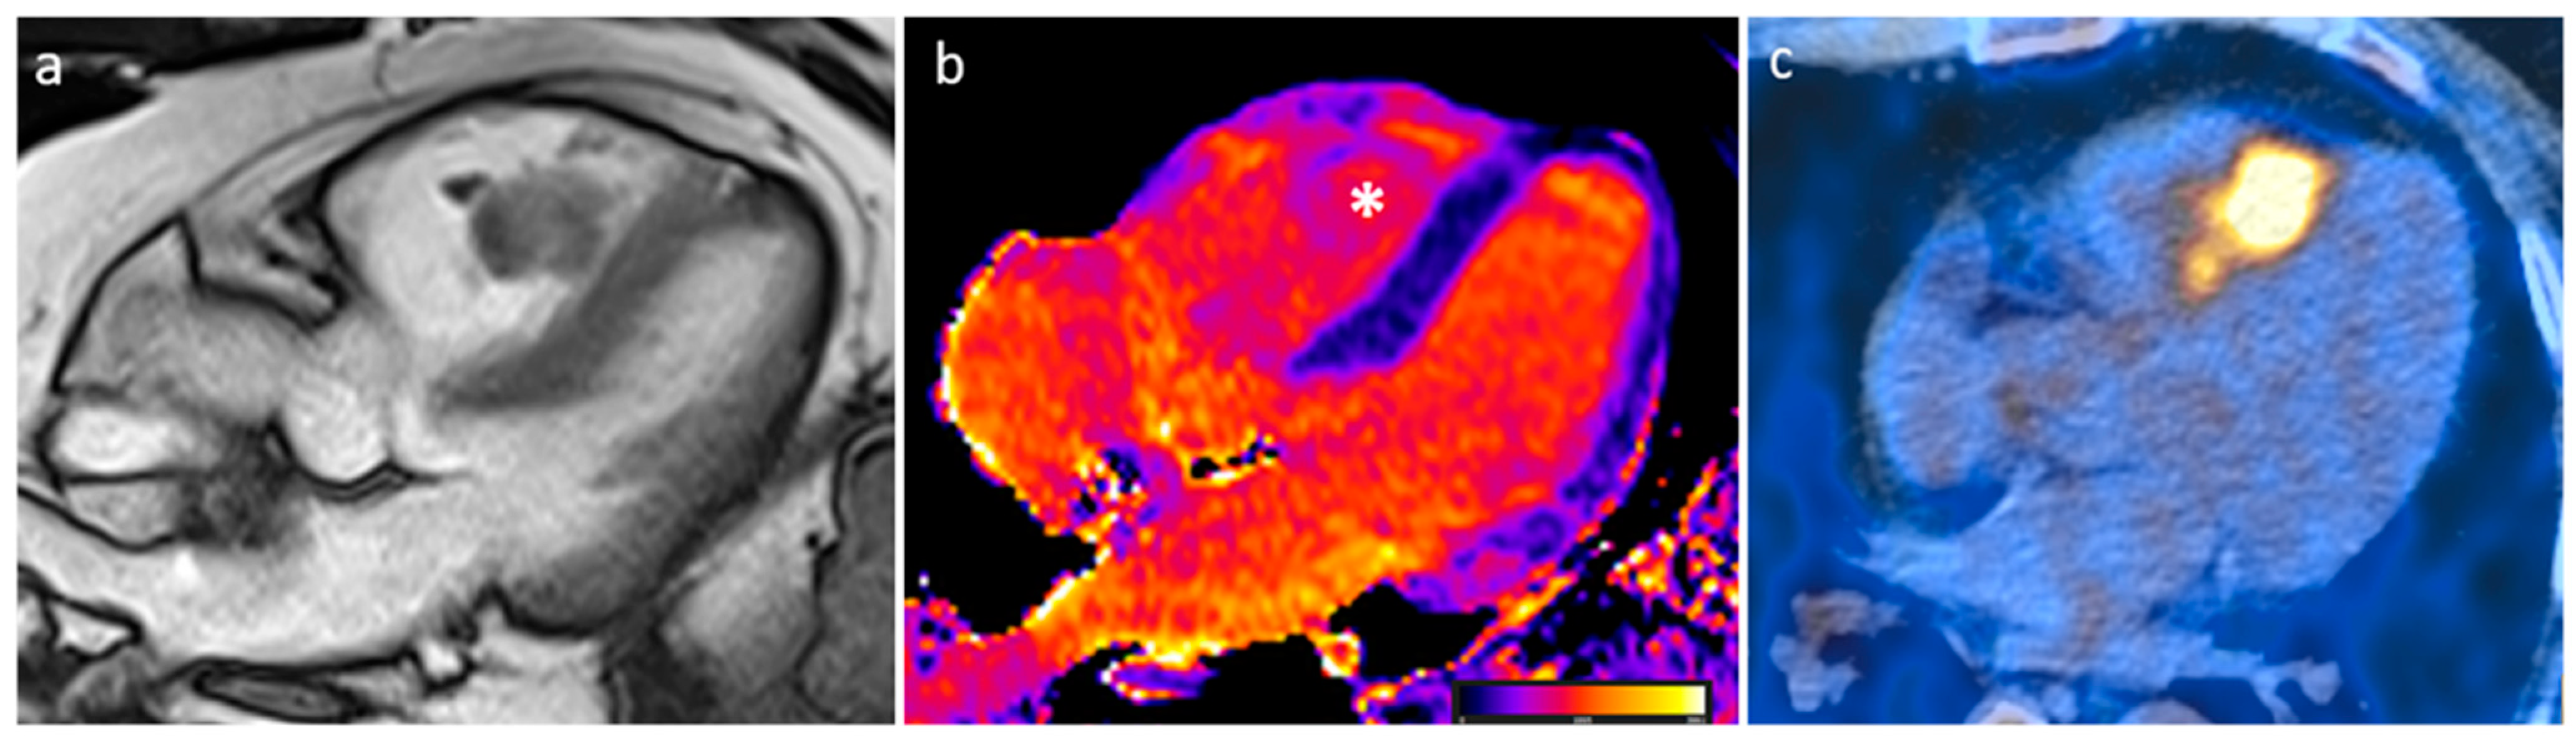

3.8. Sarcoidosis

| Sarcoidosis | Adulthood | Basal septum, AV groove | AV block, LVEF reduction | Basal septal thickening, delayed myocardial enhancement, associated mediastinal/hilar adenopathy | Septal mass lesion | Basal septum thickening, rarely soft tissue infiltration into AV groove encasing the coronary artery | LGE, Active disease (oedema): hyper T2w |